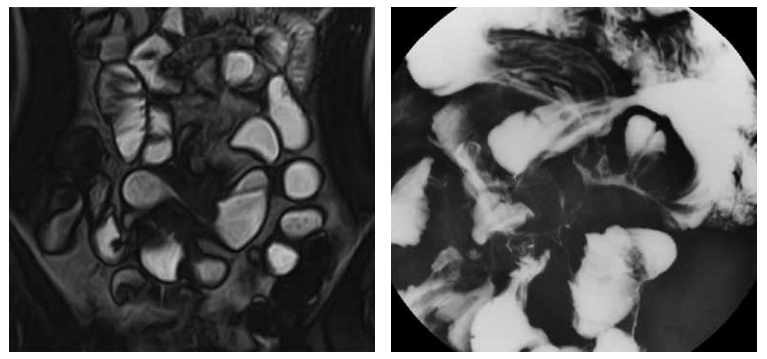

MRエンテログラフィー 1

縦走潰瘍。弧状変形を伴い、腸間膜の脈管は増強されcomb signを呈している。造影では縦走潰瘍部が増強されている。